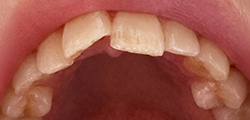

歯がガタガタ

している